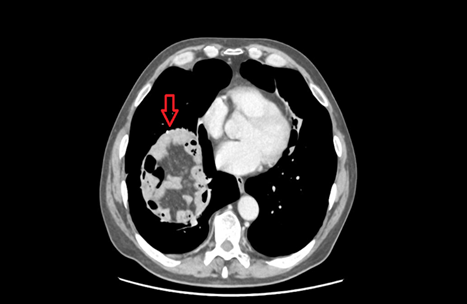

As we can see in the CT slice (pre-operative), there is fluid filled loop of small bowel which appears to have been obstructed (red arrow) in close vicinity of the heart. This loop of small bowel demonstrates poor mural enhancement and surrounding free fluid which is suggestive of bowel ischaemia but there is no evidence of free gas to suggest perforation.

Figure 1. Transverse plane of CT Chest

revealing fluid filled obstructed loop of small bowel marked by red arrow with

evidence of bowel ischemia.